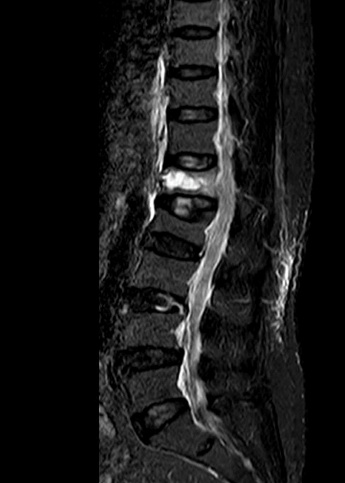

2.3. Điều trị bệnh lý cột sống: với sự hỗ trợ chuyên môn của Bệnh viện Chợ Rẫy, Bệnh viện Nhân Dân 115 TpHCM, Khoa đã và đang thực hiện phẫu thuật các trường hợp bệnh lý cột sống thắt lưng như: gãy cột sống; lấy nhân đệm thoát vị đơn thuần, qua kính vi phẫu; phẫu thuật trượt đốt sống; bơm xi-măng điều trị xẹp đốt sống do loãng xương;…Điều trị nội ngoại khoa các trường hợp Viêm thân sống đĩa đệm.

Phẫu thuật cột sống với sự hỗ trợ chuyên môn tuyến trên

Trước mổ

Sau mổ